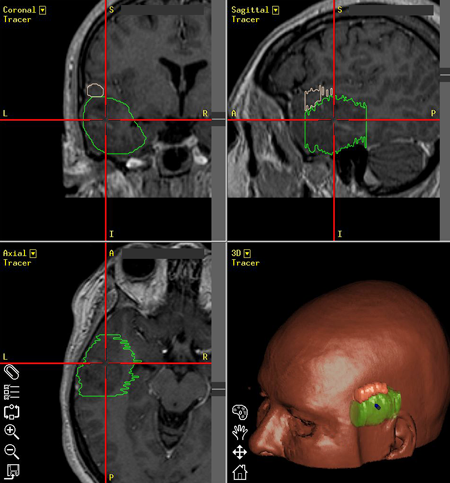

Νευροπλοήγηση σε ασθενή με κροταφικό όγκο εγκεφάλου. Ο όγκος με πράσινο περίγραμμα, η άνω κροταφική έλικα που πρέπει να διατηρηθεί με ρόζ περίγραμμα. |